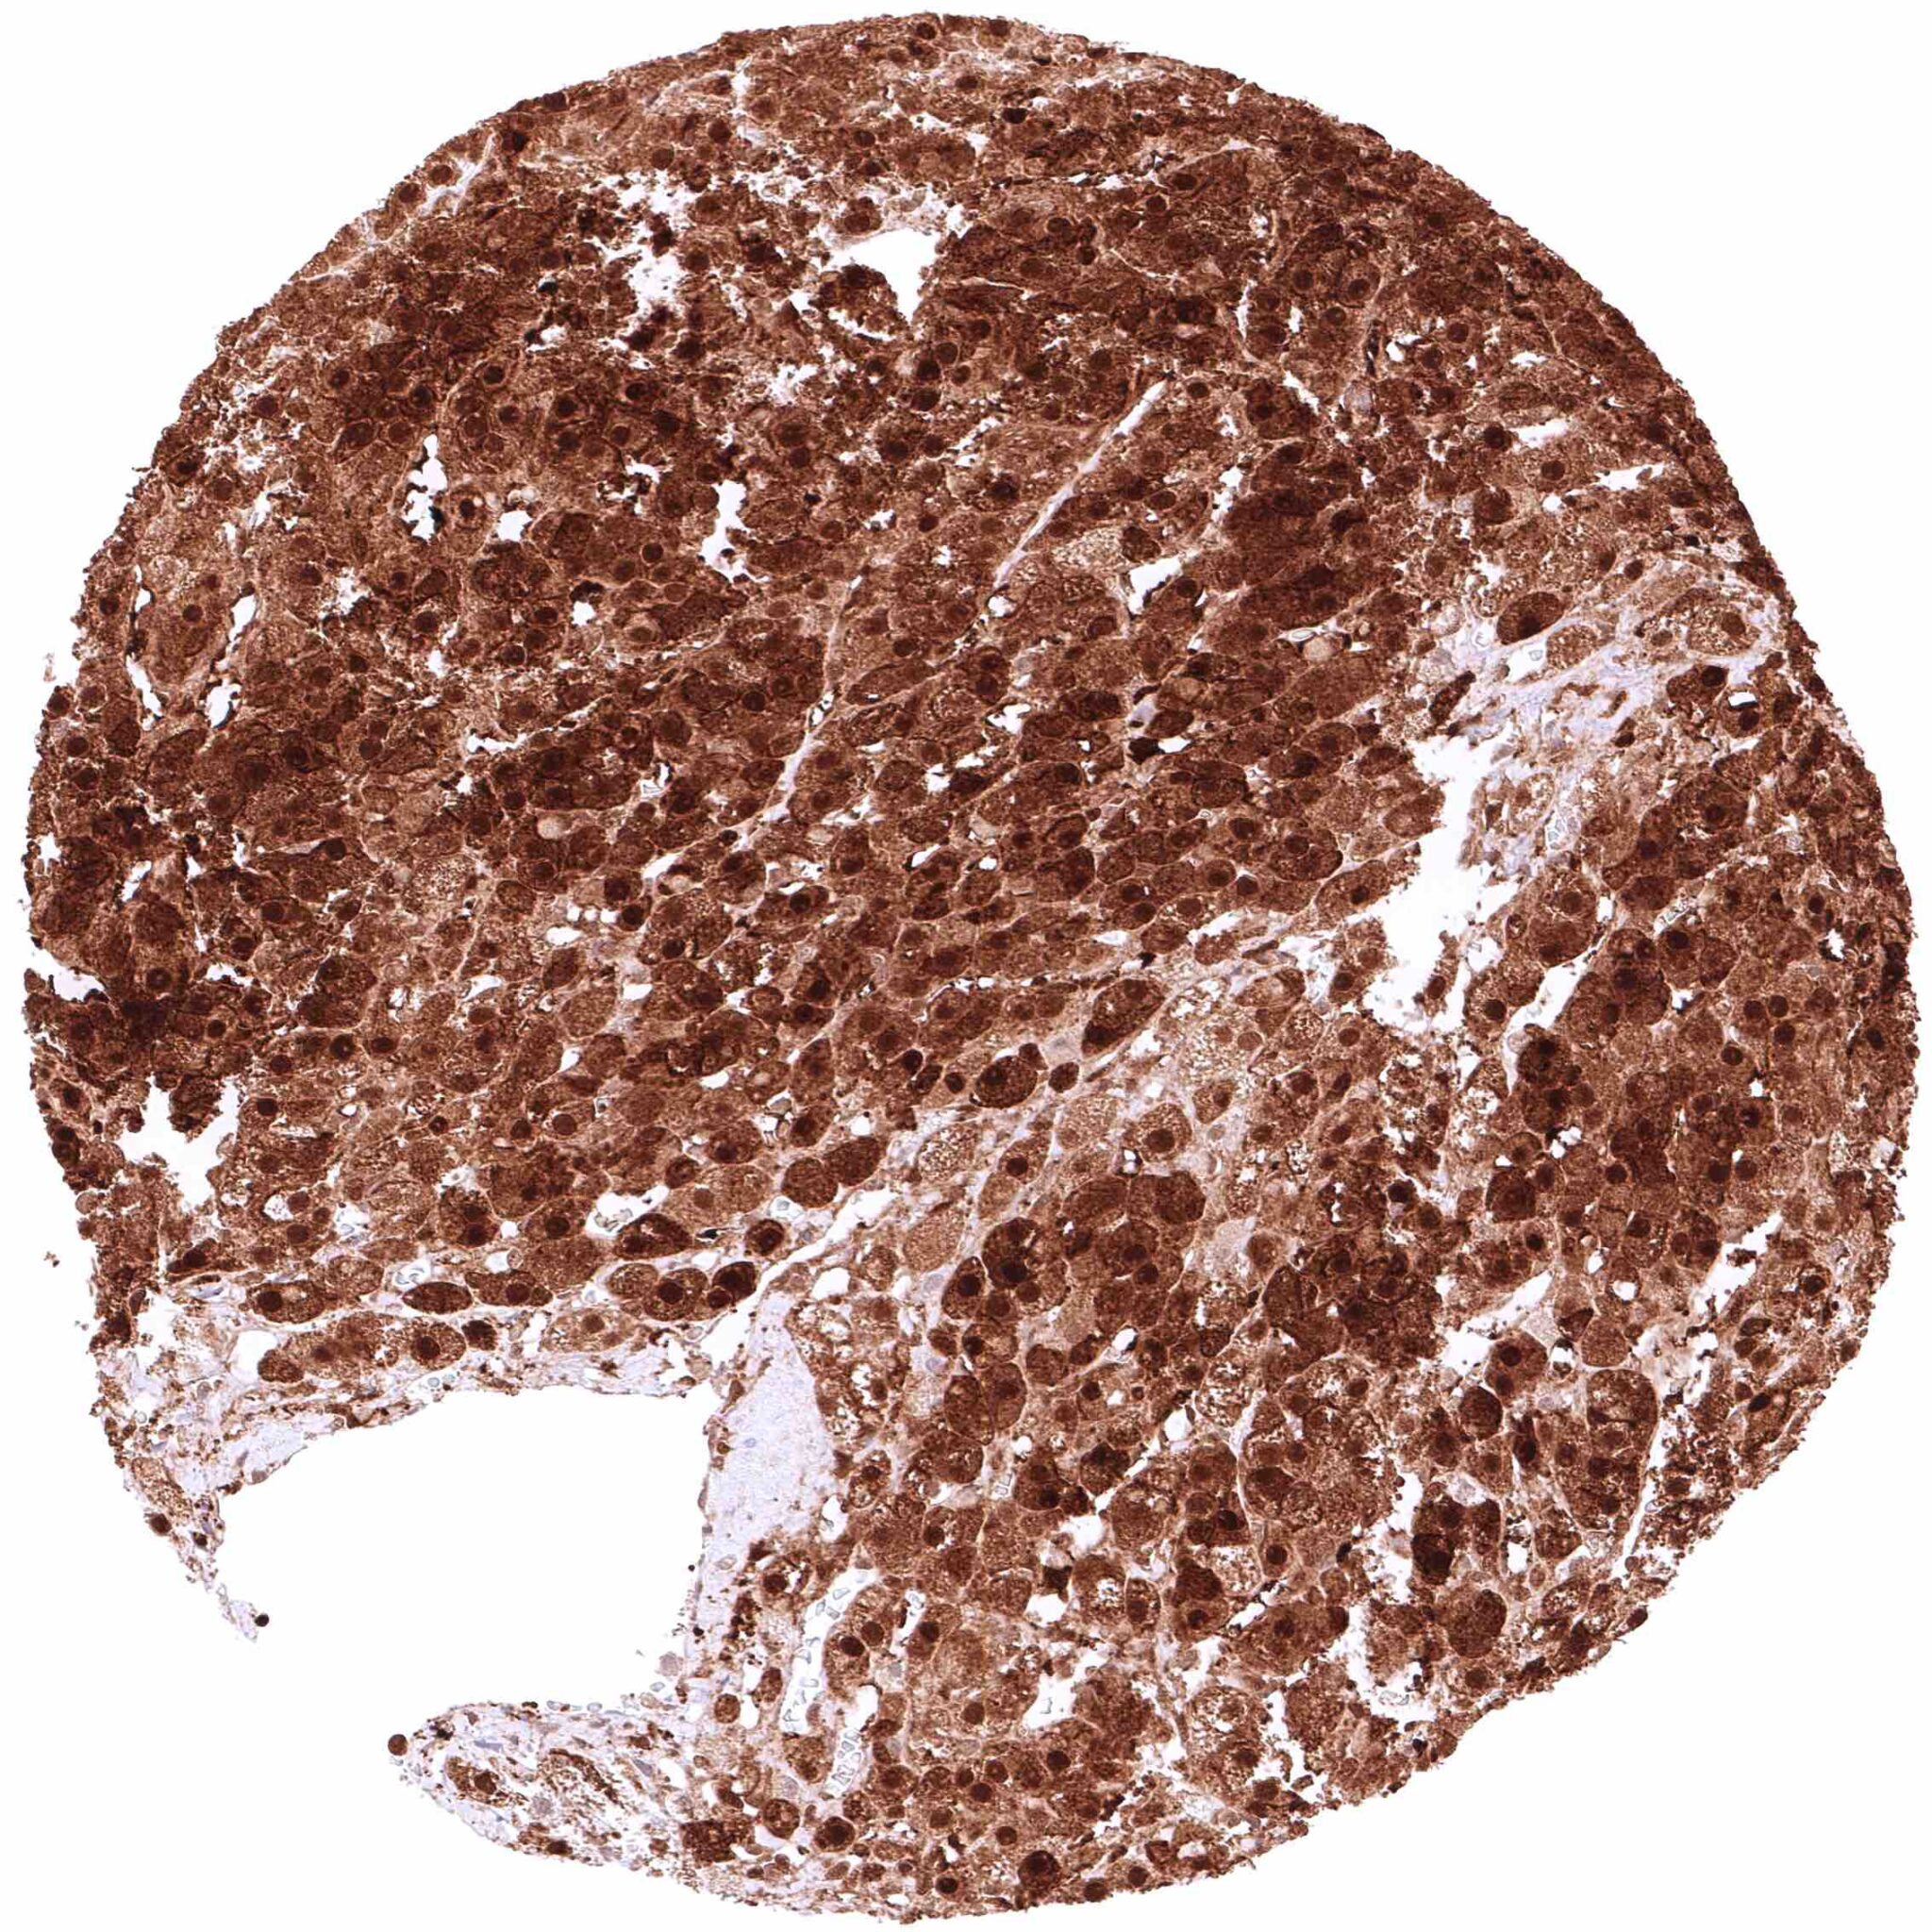

Prostate – Intense nuclear and cytoplasmic GSTP1 staining of basal cells while staining is faint or absent in acinar cells

Prostate – Intense nuclear and cytoplasmic GSTP1 staining of basal cells while staining is faint, weak or even absent in acinar cells